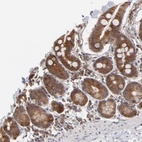

Immunohistochemical staining of human small intestine shows cytoplasmic positivity in glandular cells.